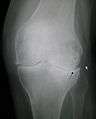

Primary osteoarthritis of the left knee. Note the osteophytes, narrowing of the joint space (arrow), and increased subchondral bone density (arrow).